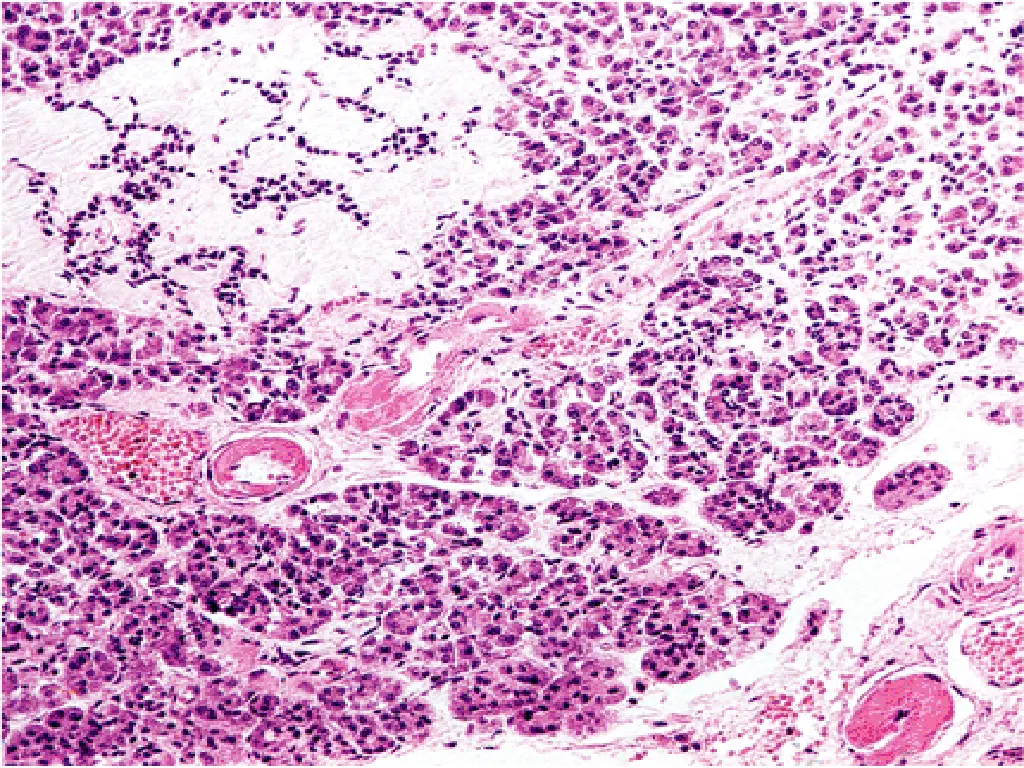

T1DM, PATHOGENESIS 2- AUTOIMMUNITY: Patients who die shortly after the onset of the disease often exhibit an infiltrate of mononuclear cells in and around the islets of Langerhans, termed insulitis 22

Insulitis 23

T1DM, Autoimmunity - Cell-mediated immune mechanisms are fundamental to the pathogenesis of T1DM ,CD8+T lymphocytes pre-dominate, although some CD4+cells are also present. - The infiltrating inflammatory cells also elaborate cytokines, for example, IL-1, IL-6, interferon-alpha, and nitric oxide, which may further contribute to B cell injury. - An autoimmune origin for T1DM was initially suggested by the demonstration of circulating antibodies against components of the B cells (including insulin itself) in most newly diagnosed children with diabetes. 24

PATHOLOGY - Lymphocytic infiltrate in the islets (insulitis), sometimes accompanied by a few macrophages and neutrophils - As the disease becomes chronic, the B cells of the islets are progressively depleted of Beta cells - Fibrosis of the islets is uncommon. - In contrast to T2DM, deposition of amyloid in the islets of Langerhans is absent in T1DM. - The exocrine pancreas in chronic T1DM often exhibits diffuse interlobular and interacinar fibrosis, accompanied by atrophy of the acinar cells. 27